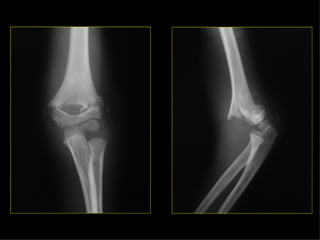

CADERA FEMUR RODILLA PIERNA TOBILLO PIE Eversión Inversión

CADERA FEMUR RODILLAPIERNA TOBILLO PIE Eversión Inversión

Estudio radiológico Ningunazona de sospecha de fractura debe tener menos de dos proyecciones con 90º entre sí. En los huesos largos (pareja en extremidades), se deben incluir ambos en su totalidad. En fracturas de extremidades son a veces necesarias proyecciones del lado normal (niños).

Estudio radiológico Elmecanismo de dolor referido puede equivocar en cuanto a la situación de la fractura, de importancia en lesiones de cadera y rodilla. Las proyecciones tangenciales son importantes en algunos huesos (planos). Deben incluirse las articulaciones más próximas a la fractura. En fracturas articulares, el estudio deberá incluir radiografías en AP, L, y ambas oblicuas, para detectar posibles fracturas verticales que pueden afectar a la superficie articular.